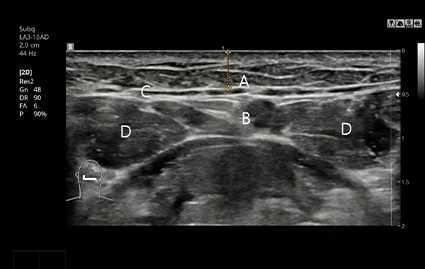

Pengambilan CT dan USG sebelum operasi

Menganalisa dengan cermat posisi dan ukuran kelenjar air liur dengan pemindaian CT dan pemeriksaan USG, melakukan operasi pengangkatan kelenjar ludah dengan cermat jika diperlukan

Pemindaian CT Sebelum Operasi